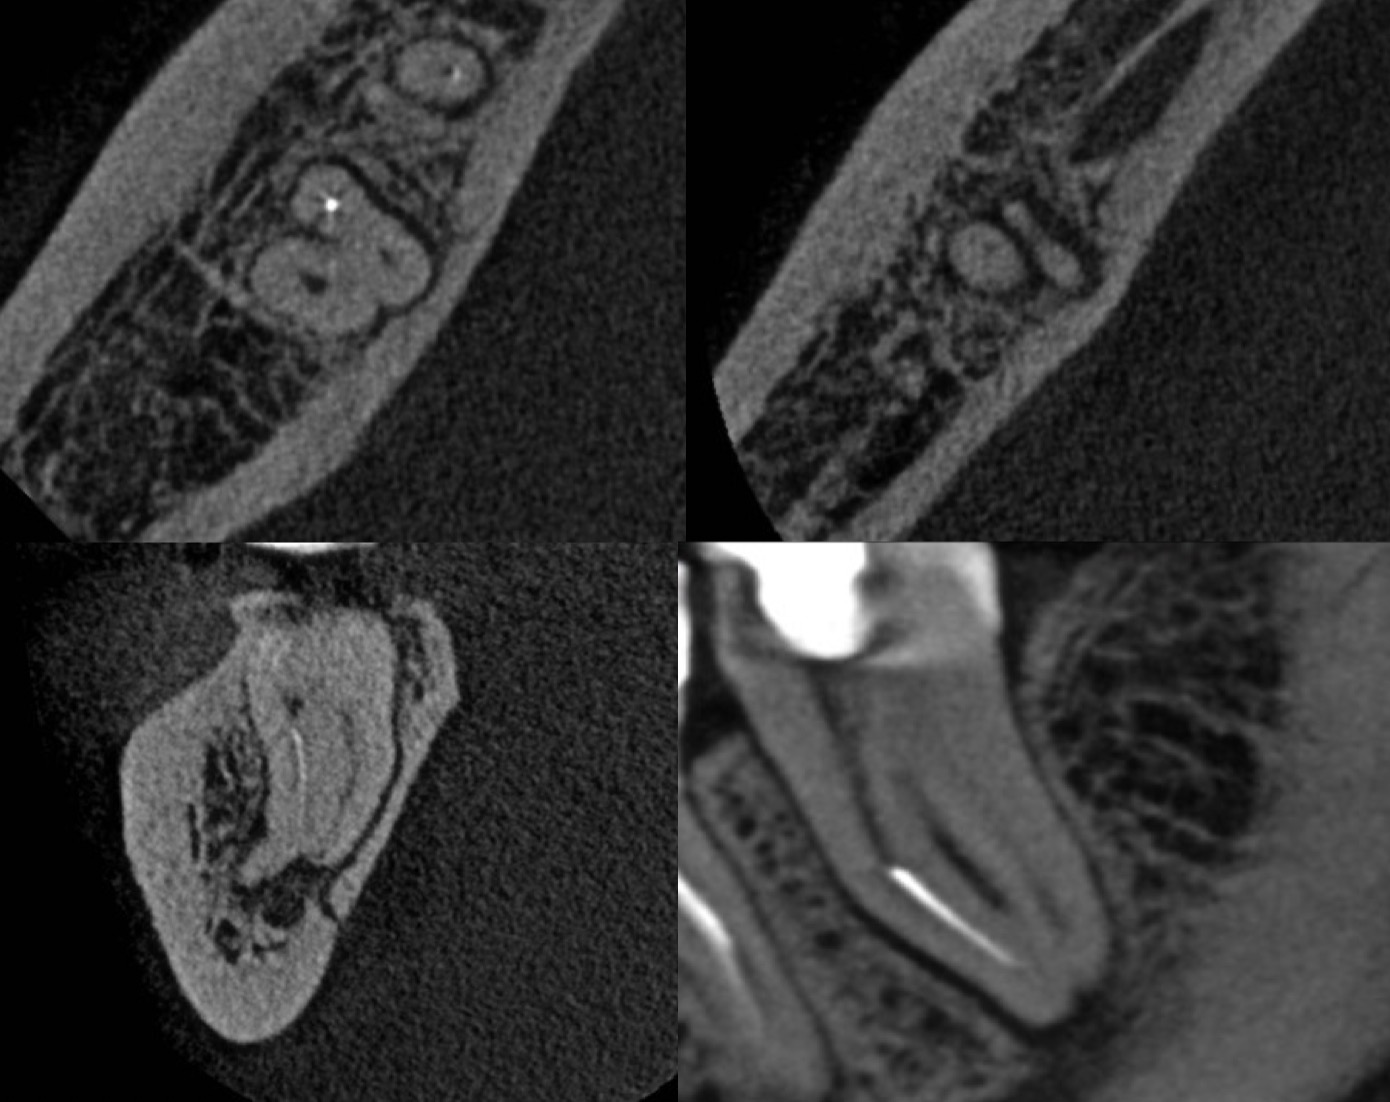

Fig. 2

CBCT Analysis

•Separated instrument beyond apical curvature (MB canal)

•Two independent mesial canals

•Thick buccal cortical plate → surgical approach limited

•Active periapical lesion close to inferior alveolar nerve